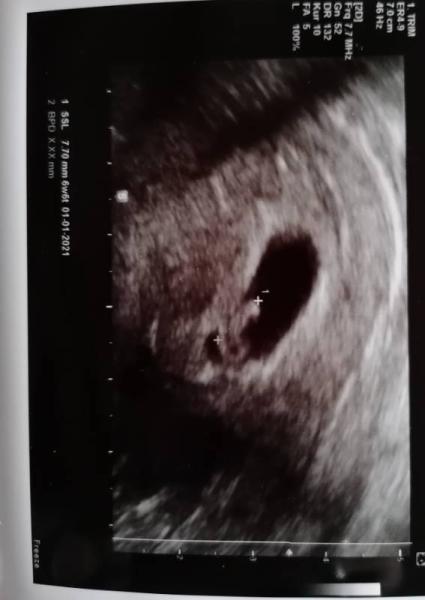

Ich Freu mich wahnsinnig im Januar 2021 das erste Mal Mama zu werden mit 36 . Hatte am 14.5. Den ersten FA Termin und man konnte das

sehen

ach ja bin 7+1. LG